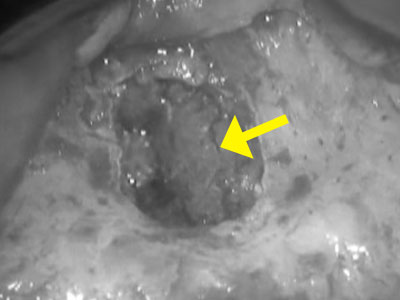

折れた破片は小さいためマイクロスコープを使用して除去を行う。

治療前

治療中にマイクロスコープで確認すると金属が見える

レントゲンで他の部分より白く写っている部分は金属片と思われる

治療後

金属を除去した状態

レントゲンを撮影すると白い部分が除去されたことがわかる